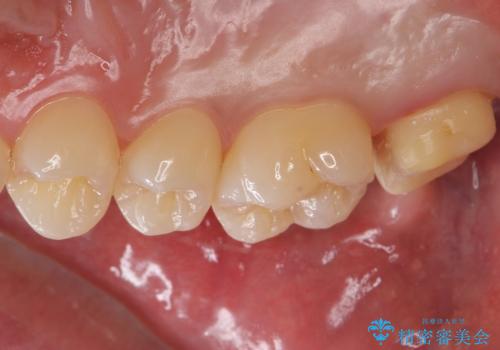

- 右上7 仮歯+ジルコニアクラウン:11,000円+121,000円費用は治療当時の料金となります

ブラッシングが上手な患者様であったため歯茎の締りもよく、大変適合の良い被せ物を装着することができました。